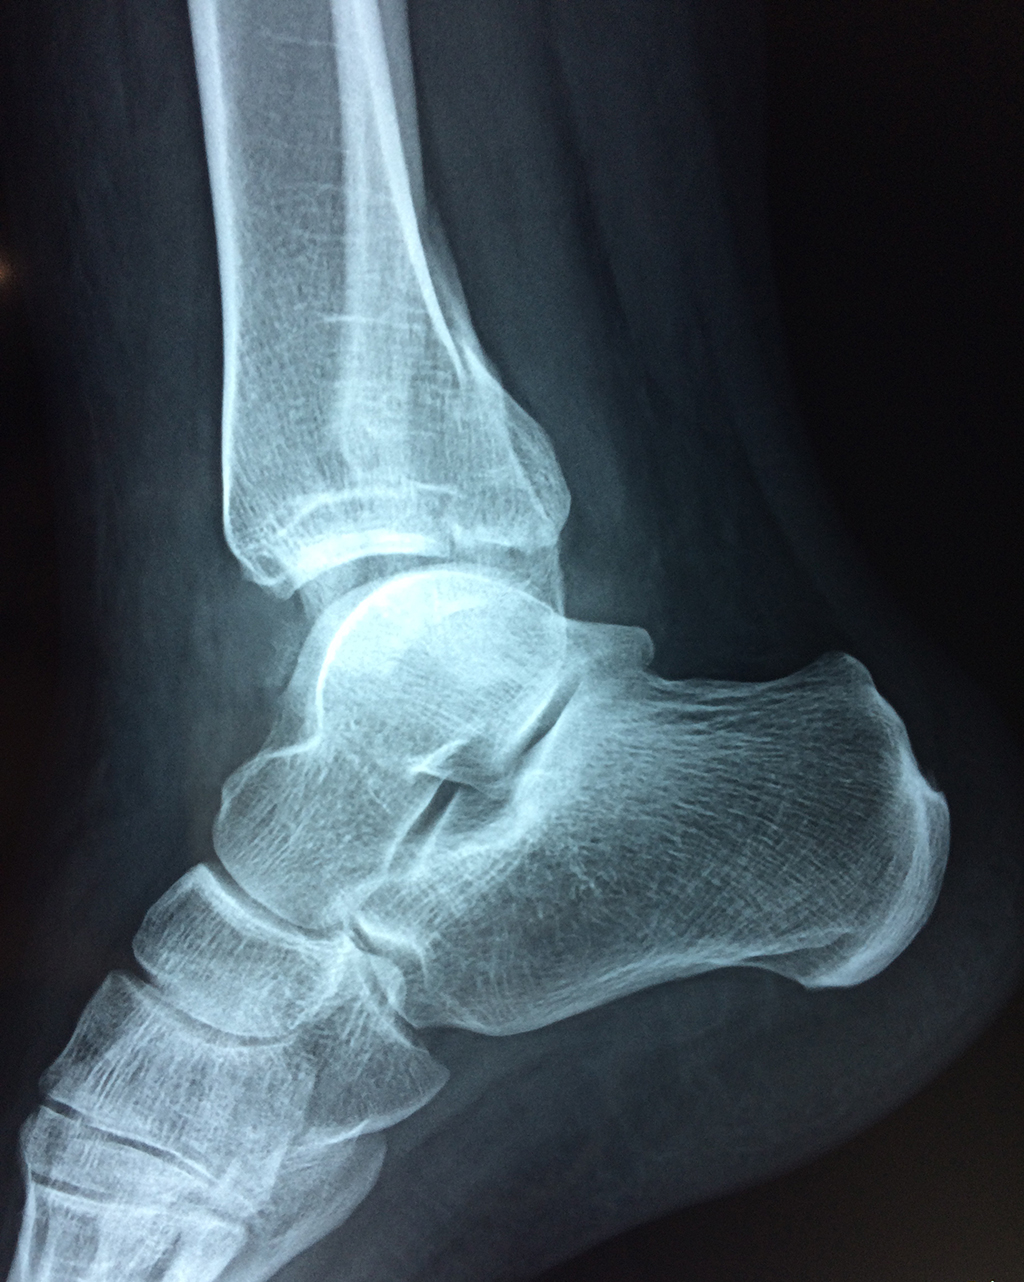

Una fractura de tobillo es la rotura de uno o más de los huesos del tobillo. Estas fracturas pueden ser:

Algunas fracturas de tobillo pueden requerir cirugía si:

- Los extremos de los huesos están desalineados entre sí (desplazados).

- La fractura se extiende hasta la articulación del tobillo (fractura intra-articular).

- Los tendones o ligamentos (tejidos que sujetan los músculos y los huesos entre sí) están rotos.

- El médico cree que sus huesos probablemente no sanen apropiadamente sin cirugía.

- El médico considera que la cirugía puede permitirle una recuperación más rápida y confiable.

- En los niños, la fractura involucra la parte del hueso del tobillo donde el hueso está creciendo.

Cuando se necesita cirugía, es probable que esta implique el uso de clavijas de metal, tornillos o placas para sostener los huesos en su lugar mientras la fractura se consolida. Los elementos de soporte pueden ser temporales o permanentes.